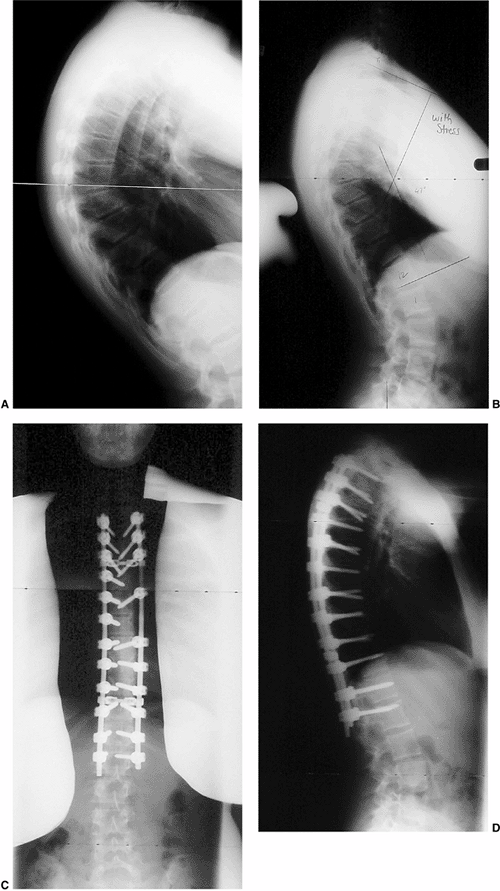

because of various opinions about pain, disability, trunk deformity,

and importance of cosmesis. Therefore, the decision for surgery must be

made on an individual basis. The current indications for surgery are a

progressive kyphosis of more than 75 degrees, or significant kyphosis

associated with pain that is not alleviated by nonoperative treatment

methods. The biomechanical principles of correction of kyphosis

secondary to Scheuermann disease include lengthening the anterior

column (anterior release), providing anterior support (interbody

fusion), and shortening and stabilizing the posterior column

(compression instrumentation and arthrodesis) (140).

Surgical correction of kyphosis can be achieved by a posterior

approach, an anterior approach, or a combined anterior and posterior

approach. The combined anterior and posterior approach has been the

most frequently recommended and reliable procedure (141,142,143,144) (Fig. 20.18).

![]() |

|

Figure 20.18 Thoracic Scheuermann kyphosis. A: Preoperative lateral radiograph. B: Stress lateral radiograph. C and D: Postoperative status of posterior instrumentation and fusion with pedicle screws. (Courtesy of Dr. Anant Kumar.)